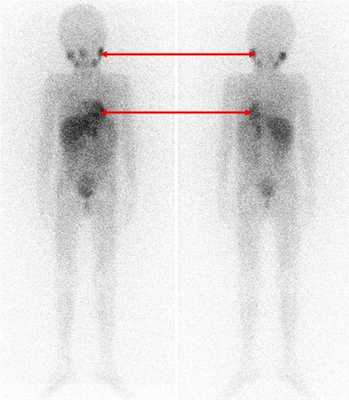

Радиоизотопные исследования

Одним из наиболее информативных специфических методов топической диагностики нейробластом является сцинтиграфия с метайодбензилгуанидином (МЙБГ), меченным 123I. МЙБГ по своей химической структуре сходен с катехоламинами в организме. Это вещество концентрируется в тех опухолях, которые вырабатывают катехоламины. МЙБГ метят радиоактивным изотопом йода (например, 123I) в безопасной для жизни дозе, и готовый препарат внутривенно вводят в кровоток. Накапливаясь в клетках опухоли, он дает излучение. Эти сигналы регистрирует специальная камера и переводит их в изображение. Таким образом, метод позволяет выявить не только первичную опухоль, но и наличие регионарных и отдаленных метастазов (рис. 7).

![Рис. 7. Сцинтиграфия с метайодбензилгуанидином (визуализируется первичная паравертебральная опухоль с метастазами в кости черепа)]()

Рис. 7. Сцинтиграфия с метайодбензилгуанидином (визуализируется первичная паравертебральная опухоль с метастазами в кости черепа)